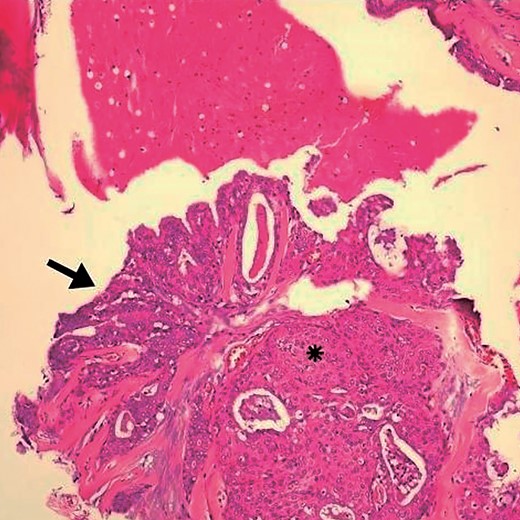

Arrows indicate the wall of a multilocular cyst without atypias. Black asterisk – non-invasive solid area with epidermoid alterations and low-grade atypias. White asterisk – invasive area with squamous and mucinous elements, suggesting the possibility of mucoepidermoid carcinoma. HE, ×4.

A 45-year-old female patient, who denied smoking and alcohol consumption, experienced sudden discomfort in the right parotid region with an increase in volume for a week. The discomfort lasted two days and stopped after the prescription of non-hormonal anti-inflammatories. Although the discomfort passed, the volume continued to increase. The patient denied xerostomia, a history of rheumatoid arthritis, fever, and weight loss. On palpation, a firm, deep nodular lesion measuring 5 × 4 cm was detected, forming part of the right parotid gland. Ultrasonography confirmed the diagnosis of a right parotid cyst measuring 29 × 19 × 21 mm. Fine needle aspiration cytology (FNAC) was performed, with a diagnosis of chronic parotid cyst. As the lesion persisted and increased in volume, surgery was recommended; however, the patient chose to continue with observation. In subsequent examinations, the size of the lesion increased, measuring 6 × 4 cm. She underwent right partial parotidectomy with preservation of the facial nerve, with good evolution. In the context of the cystic lesion, a well-differentiated intracystic, well-defined mucoepidermoid microcarcinoma was diagnosed, with discrete cytological atypia (Figs 1 and 2). The patient remains under periodic follow-up, with no evidence of disease after six months.